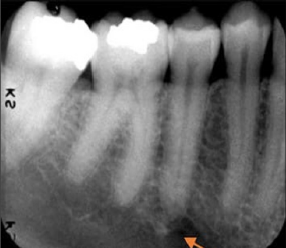

60. What is showing by arrow?

Submandibular Gland Fossa a bone depression on the lingual surface of the mandibular body, immediately below the mylohyoid ridge in the molar area. often appears as a radiolucent area with the sparse trabecular pattern